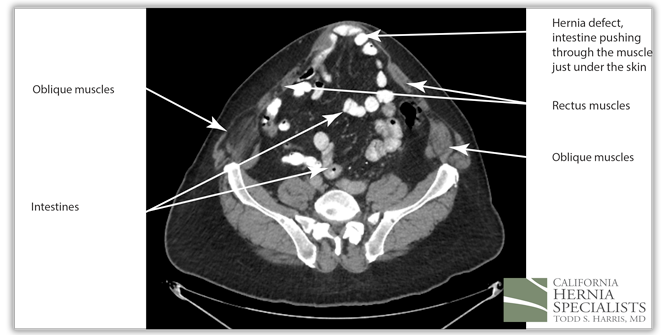

However, in this CAT scan image, there is a noticeable hole in the lower muscle wall, and the start of an inguinal hernia both on the left and the right side of the groin.

The patient sought a second opinion at California Hernia Specialists where we reviewed his CAT scan and examined his abdomen. It was clear that although his muscles had weakened, there was also a definite hole in the muscle and a recurrent incisional hernia. His small bowel and internal fat was protruding through the hole contributing to his bulge.

The 3 CAT scan images below show the patients normal muscles above the hernia, then a large hernia defect or hole in the muscle, and then the normal muscles again below the hernia defect.

The CAT scan image below compares the patient before surgery, and then after surgery when the muscle has been pulled back together and the hernia has been repaired.